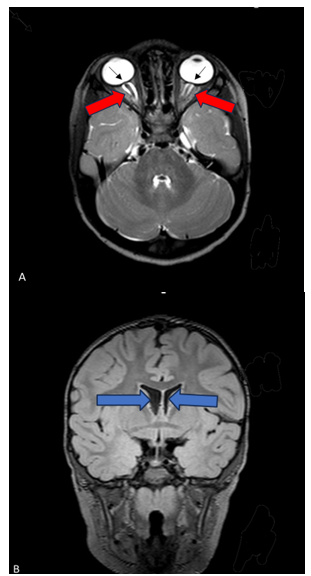

While awaiting consent to perform the magnetic resonance imaging, the patient was evaluated by neuro-ophthalmology. This examination confirmed moderate and diffuse bilateral optic disc edema. Notably, the patient remained asymptomatic. The magnetic resonance imaging was finally performed two months after the initial eye appointment. The imaging demonstrated posterior globe flattening bilaterally and prominent cerebral spinal fluid in the optic nerve sheaths, as well as evidence of the prior cranial vault reconstruction. The patient’s imaging did not suggest cranio-cephalic disproportion that could lead to increased intracranial pressure (ICP) given reassuring normal ventricle size. Therefore, neurosurgery ordered magnetic resonance venography (MRV) of the brain to evaluate for possible venous sinus thrombosis as the cause of optic disc edema. The magnetic resonance venography was unremarkable. Given the persistent concern for true optic disc edema rather than pseudo-edema, and evidence of increased intracranial pressure on magnetic resonance imaging, his neurosurgery team recommended that he undergo a period of intracranial pressure monitoring to assess for elevated intracranial pressure. After several months of delay, due to challenges in obtaining consent for the procedure, the patient underwent surgery to place a Camino intracranial pressure monitor (Natus Medical, US). No cerebral spinal fluid was drained or lost during placement of the device.

Figure 2 MRI imaging Axial 3D T-2 weighted MRI image depicting posterior globe flattening (black arrows) bilaterally and prominent cerebral spinal fluid in the optic nerve sheaths (red arrows) (A). Coronal 3D FLAIR MRI image demonstrating normal ventricle size (blue arrows) (B).